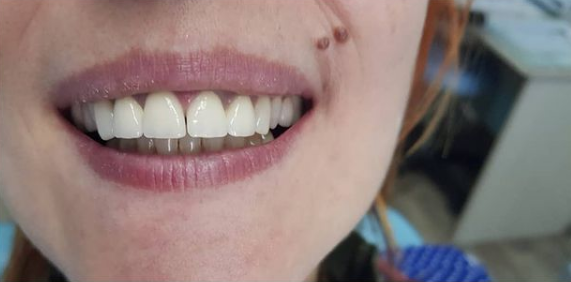

Установка коронки из диоксида циркония

Пациент, 35 лет обратился в клинику для получения консультации у стоматолога-ортопеда по причине проблем с внешним видом зубов. В результате проведенной реставрации с применением коронок из диоксида циркония было достигнуто максимальное сходство с естественным оттенком пациента.